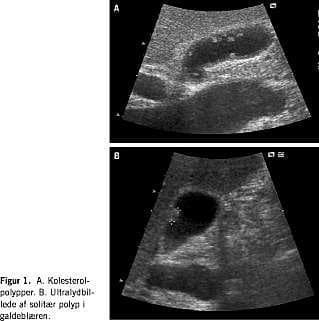

• Galdeblærepolypper ses på ultralydskanninger som små vægstillede hyperekkogene processer, der prominerer ind i lumen uden at kaste stenskygge (Figur 1 ).

• »Polypper« i galdeblæren kan være adenomer, kolesterolpolypper, slimhindefolder eller galdesten.

• Multiple polypper er ofte kolesterolpolypper, og de er ofte benigne. Solitære polypper er oftere adenomer. De bredbasede polypper er mere malignitetssuspekte end de stilkede.